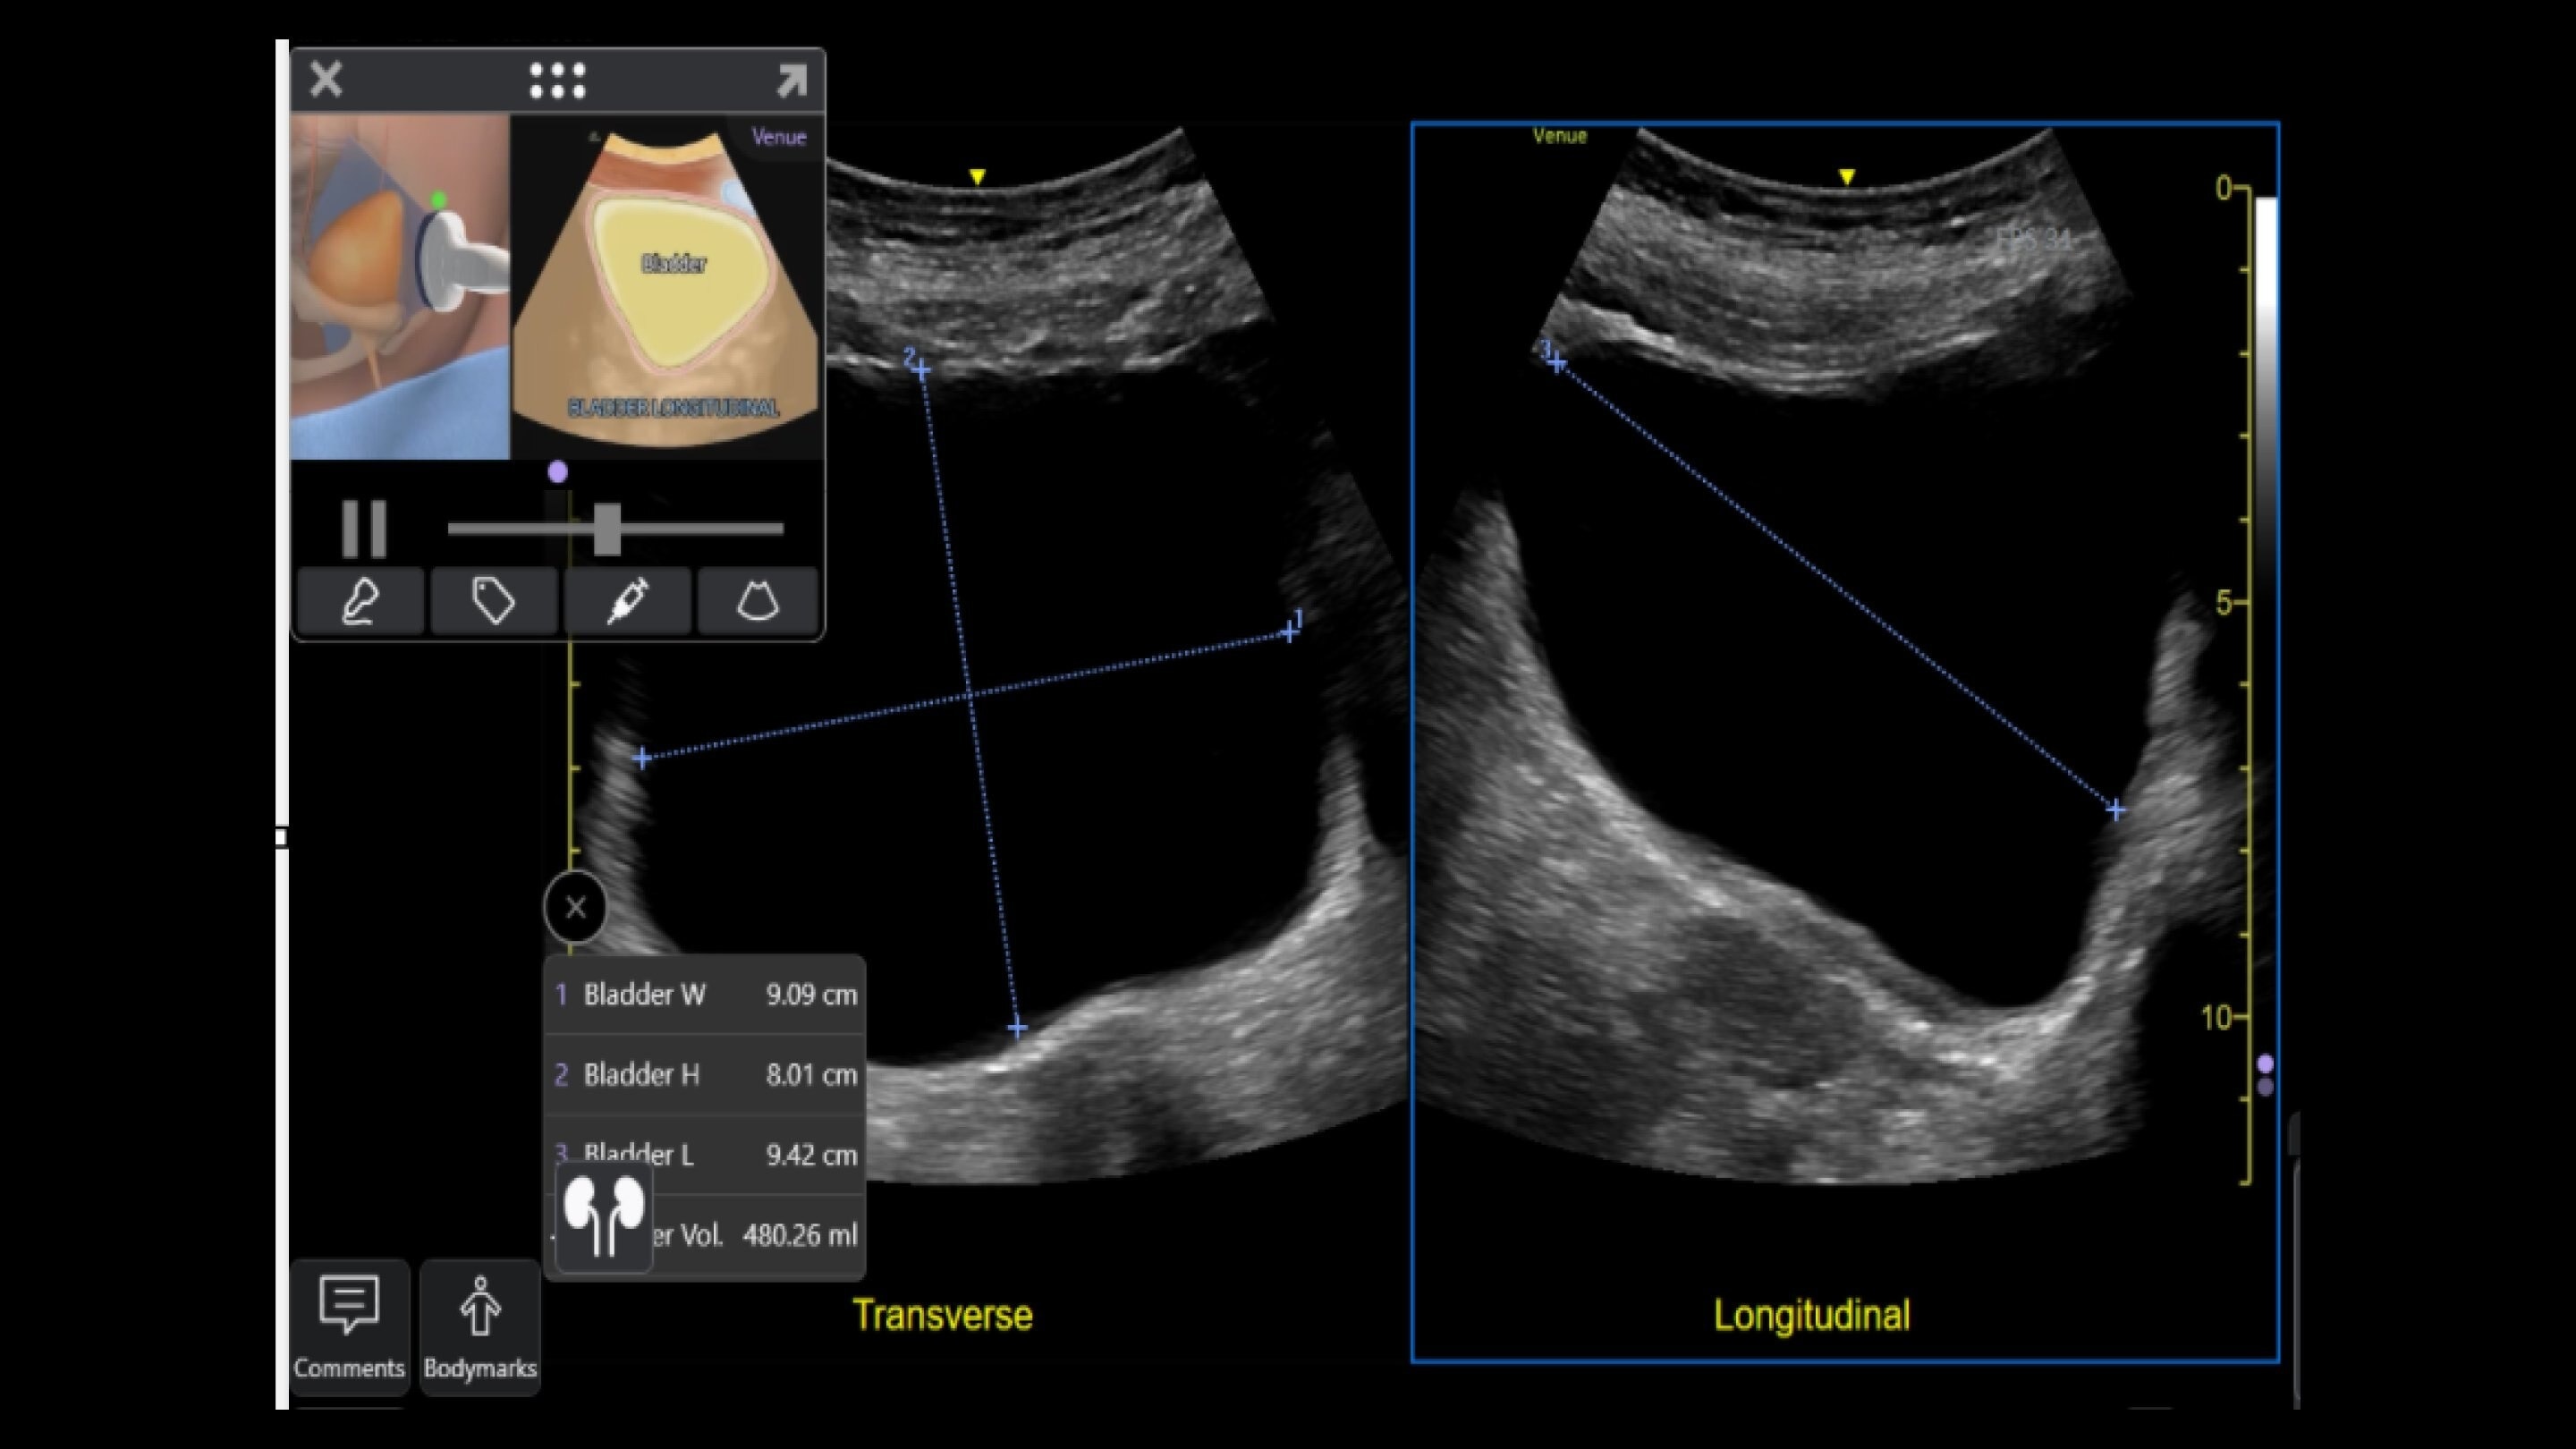

Wireless probe integration

Sync up and go - without wires you’re not tethered to a system or a space

Small yet powerful

Flexible, wireless dual-probes deliver clear images and Venue family software